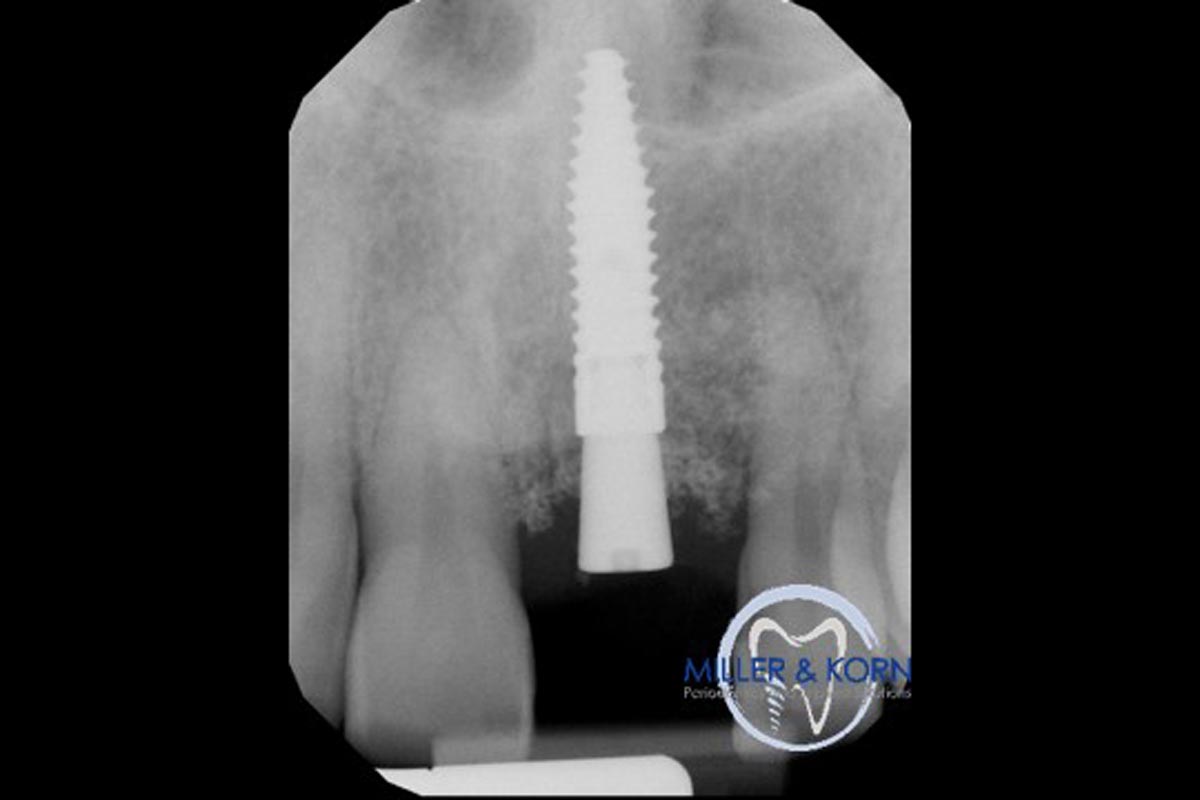

34/39 - Preoperative radiographImmediate implant placement and correction of horizontal and vertical bone loss using an allograft bone ring, cerabone® and Jason® membrane - Drs. Miller and Korn

35/39 - Immediate post surgery radiographImmediate implant placement and correction of horizontal and vertical bone loss using an allograft bone ring, cerabone® and Jason® membrane - Drs. Miller and Korn

36/39 - Radiograph 6 months after implantationImmediate implant placement and correction of horizontal and vertical bone loss using an allograft bone ring, cerabone® and Jason® membrane - Drs. Miller and Korn

37/39 - Final radiograph revealing both horizontal and vertical augmentation of the osseous defects (8 months after implantation)Immediate implant placement and correction of horizontal and vertical bone loss using an allograft bone ring, cerabone® and Jason® membrane - Drs. Miller and Korn